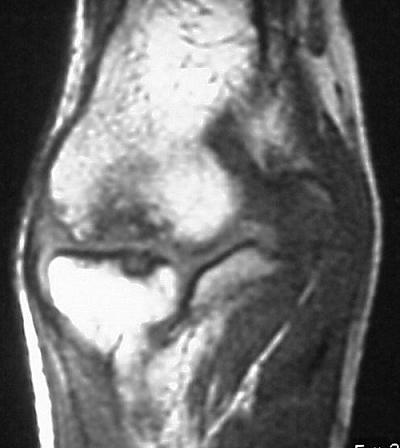

MRI shows an osteochondral sequestrum of the anterior capitellum: